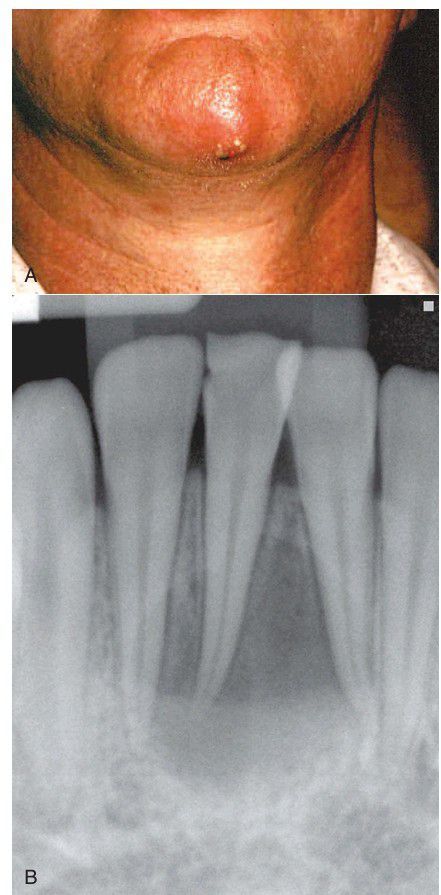

A, Extraoral sinus tract opening on the skin in the central chin area. B, Radiograph of mandibular incisors and canine after root canal therapy.